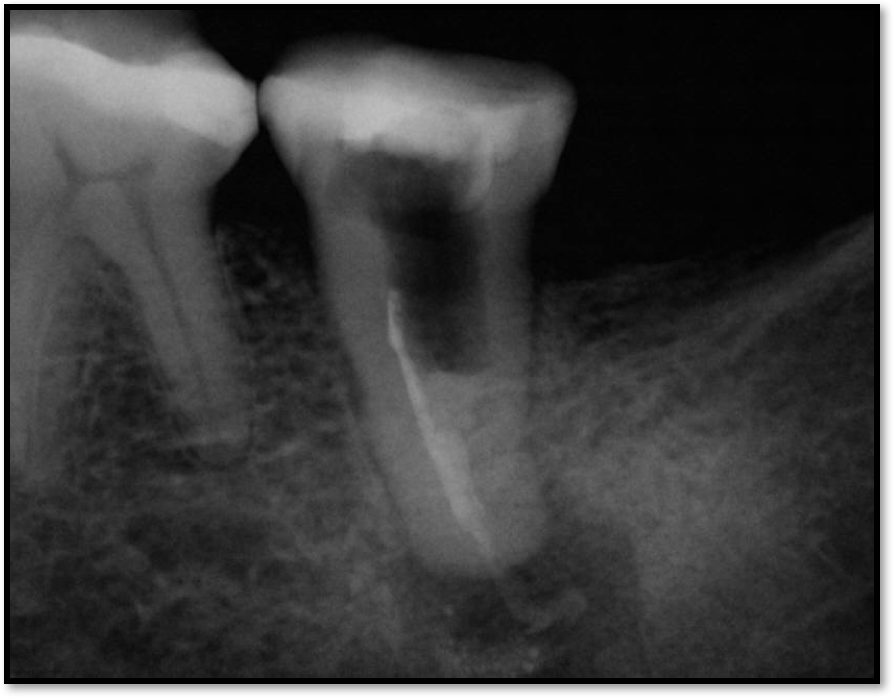

Figure 9 shows a situation on tooth No. 12 that may have been presumed to be easily resolvable. However, the dentist experienced problems, including significant bleeding. It was due either to irreversible pulpitis or a perforation. Judging by the PA, something detrimental was occurring with the distal. A lesson that can be learned from this case is that a solution does not have to look pleasant for it to work. Functionally, the repair shown in Figure 10 was successful because the clinician was able to fix the whole wall with mineral trioxide aggregate (MTA) and was able to find the canal. The clinician also put in the post for the general dentist and closed it. Later, the general dentist took the post out and replaced it with a post that was larger and shorter than would be recommended. Interestingly, the result lasted 8.5 years, as shown in Figure 11.

The clinician took the path described because the patient initially came in with some sensitivity on the tooth, but the issue quickly progressed to the need for a root canal and the possibility of losing the tooth because her general dentist had inadvertently destroyed the wall. Unfortunately, the story does not have a happy ending: at 9.25 years, the repairs finally broke. Yet the case is important because it shows that a resolution for even a “terrible” case can last almost 10 years and be to some extent a success. When the right principles are maintained, there can still be a successful outcome. The reason this case in particular succeeded was because of a factor that was barely visible: above the perforation repair was 2 mm of ferrule and, therefore, coronal tooth structure. The perforation was not only below the gum but also the bone, which is generally a more ideal location for a perforation.

Fig 12. The post was too long.

Figure 12

Fig 13. A good root canal may have been absorbed.

Figure 13